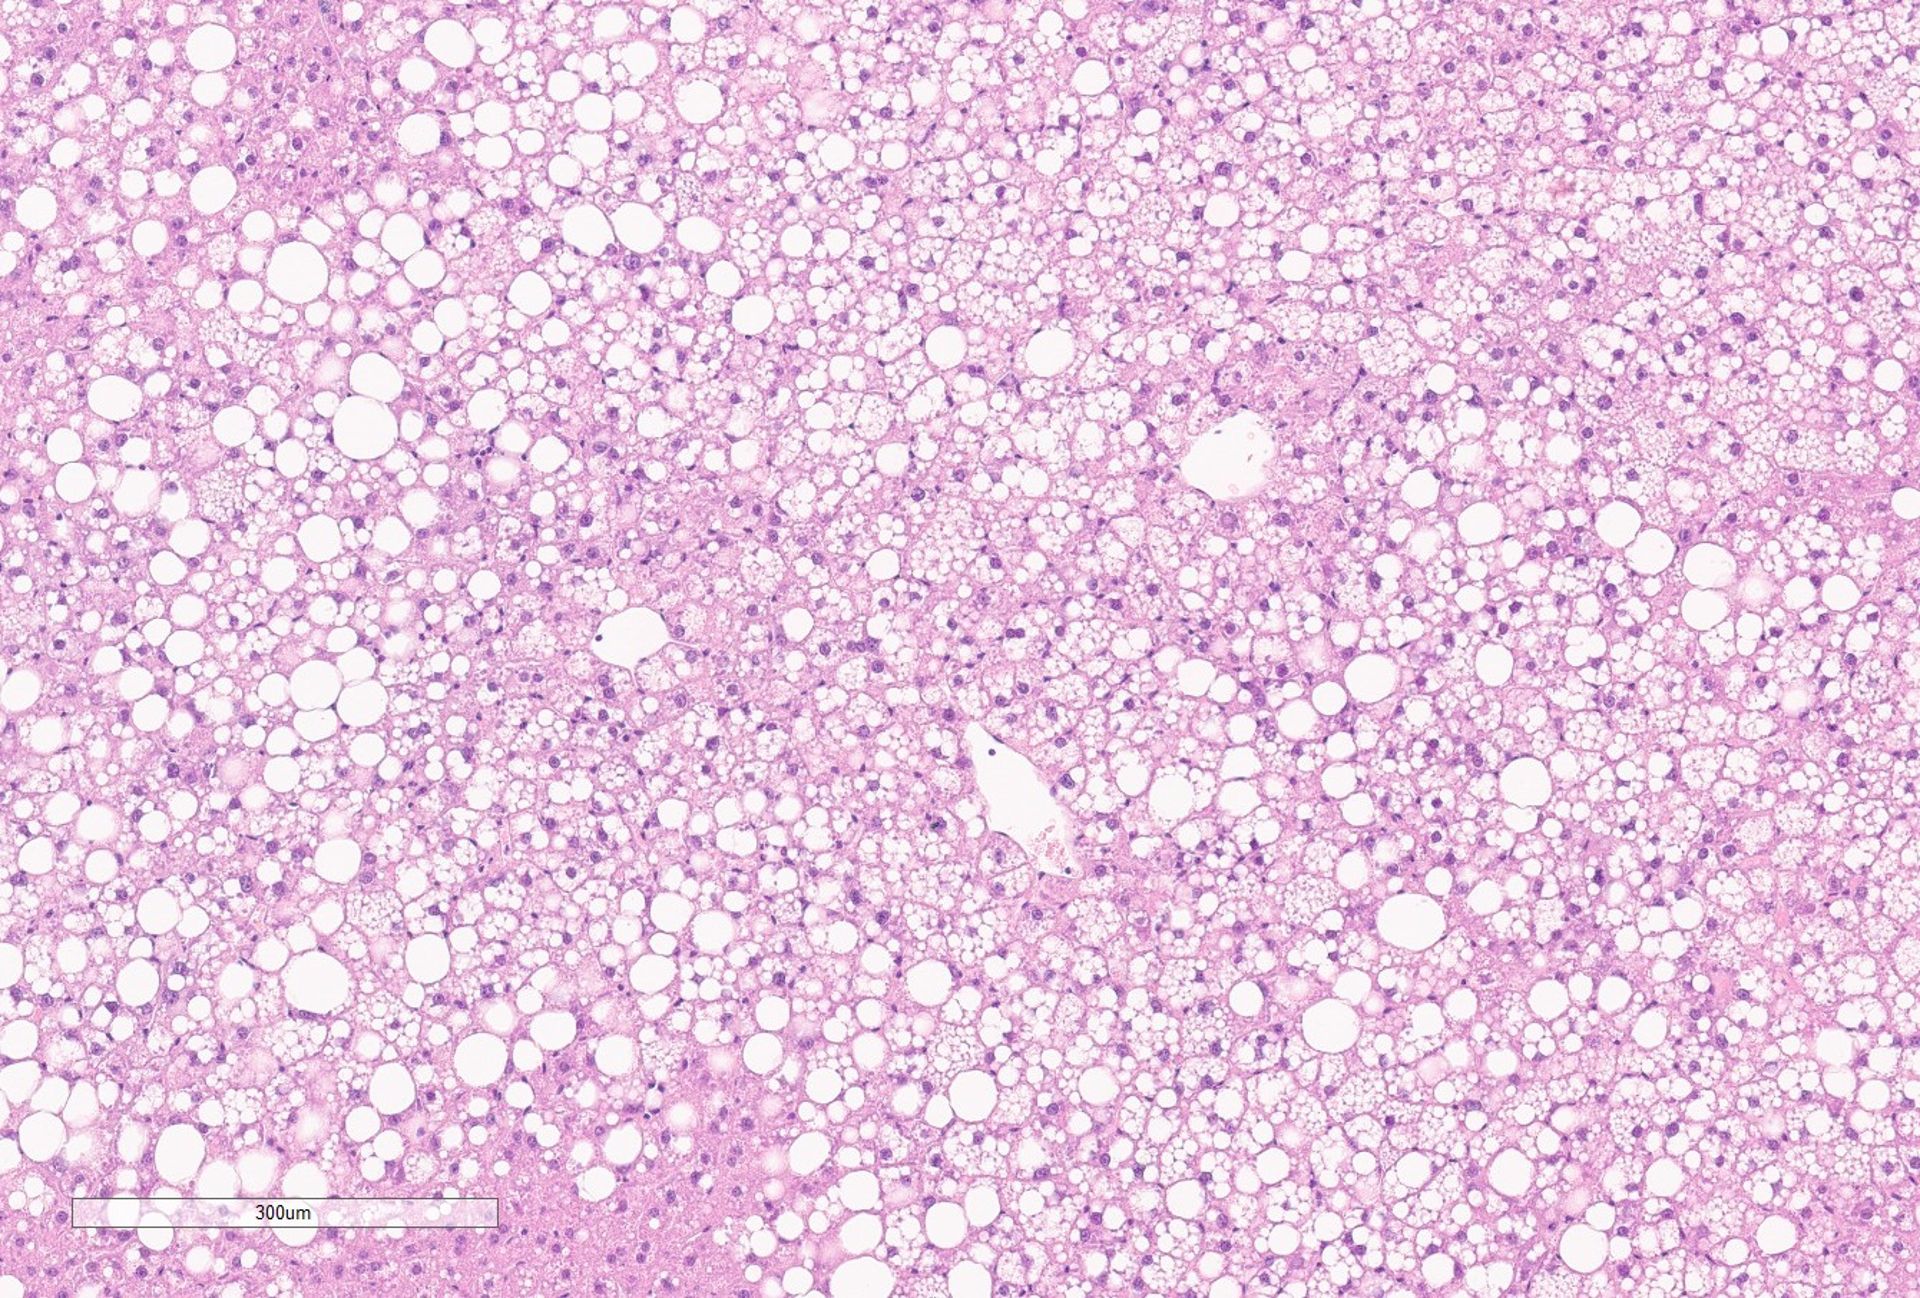

La deficienza del recettore della leptina (LEPRD) è una malattia genetica congenita in cui il cervello non regola più in maniera ottimale i segnali dell’appetito e dell’equilibrio energetico.

Questo causa iperfagia (la tendenza a mangiare molto), aumento del glucosio nel sangue e aumento della resistenza insulinica, portando a una forma di obesità pediatrica molto grave.

Il progetto della Dott.ssa Laura Silvestri mira a sviluppare strategie terapeutiche basate su oligonucleotidi antisenso che bersagliano una via chiave di regolazione del metabolismo epatico.

Grazie a dati recentemente generati dal mio gruppo, abbiamo dimostrato che l’attivazione della via di segnale BMP-SMAD tramite oligonucleotidi antisenso mirati al fegato è sufficiente a migliorare il metabolismo dei lipidi e degli zuccheri. Combinando modulazione genica mirata e regolazione dell’appetito, vogliamo correggere il difetto metabolico alla base della LEPRD. L’obiettivo è non solo intervenire su questa specifica patologia, ma estendere l’approccio ad altre forme di obesità genetica e disturbi metabolici rari.